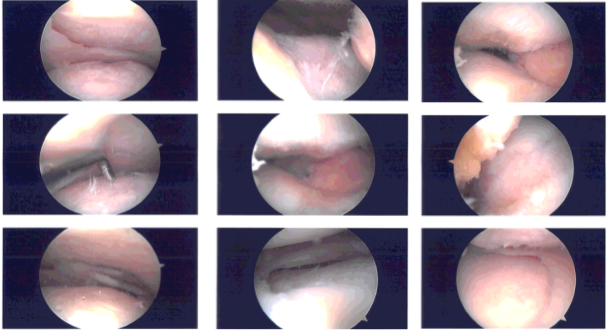

Examination of the knee was performed which showed a tear of the lateral freeing margin of the medial meniscus as well as tear of the medial freeing margin of the lateral meniscus along with discoid lateral meniscus. The ACL was intact. Meniscectomy was performed with the use of biters and shavers.

Saucerization of the lateral meniscus was also confirmed. The root as well as the periphery of the medial and lateral meniscus were intact. The ACL was intact.

Examination of the patellofemoral joint showed grade 1 to grade 2 arthritis on the lateral facet of the patella as well as grade 3 to grade 4 arthritis of the trochlea. Chondroplasty of the patella as well as trochlea was performed with the use of shaver and Coblation wand. Final pictures were taken and saved.

Intraoperative images